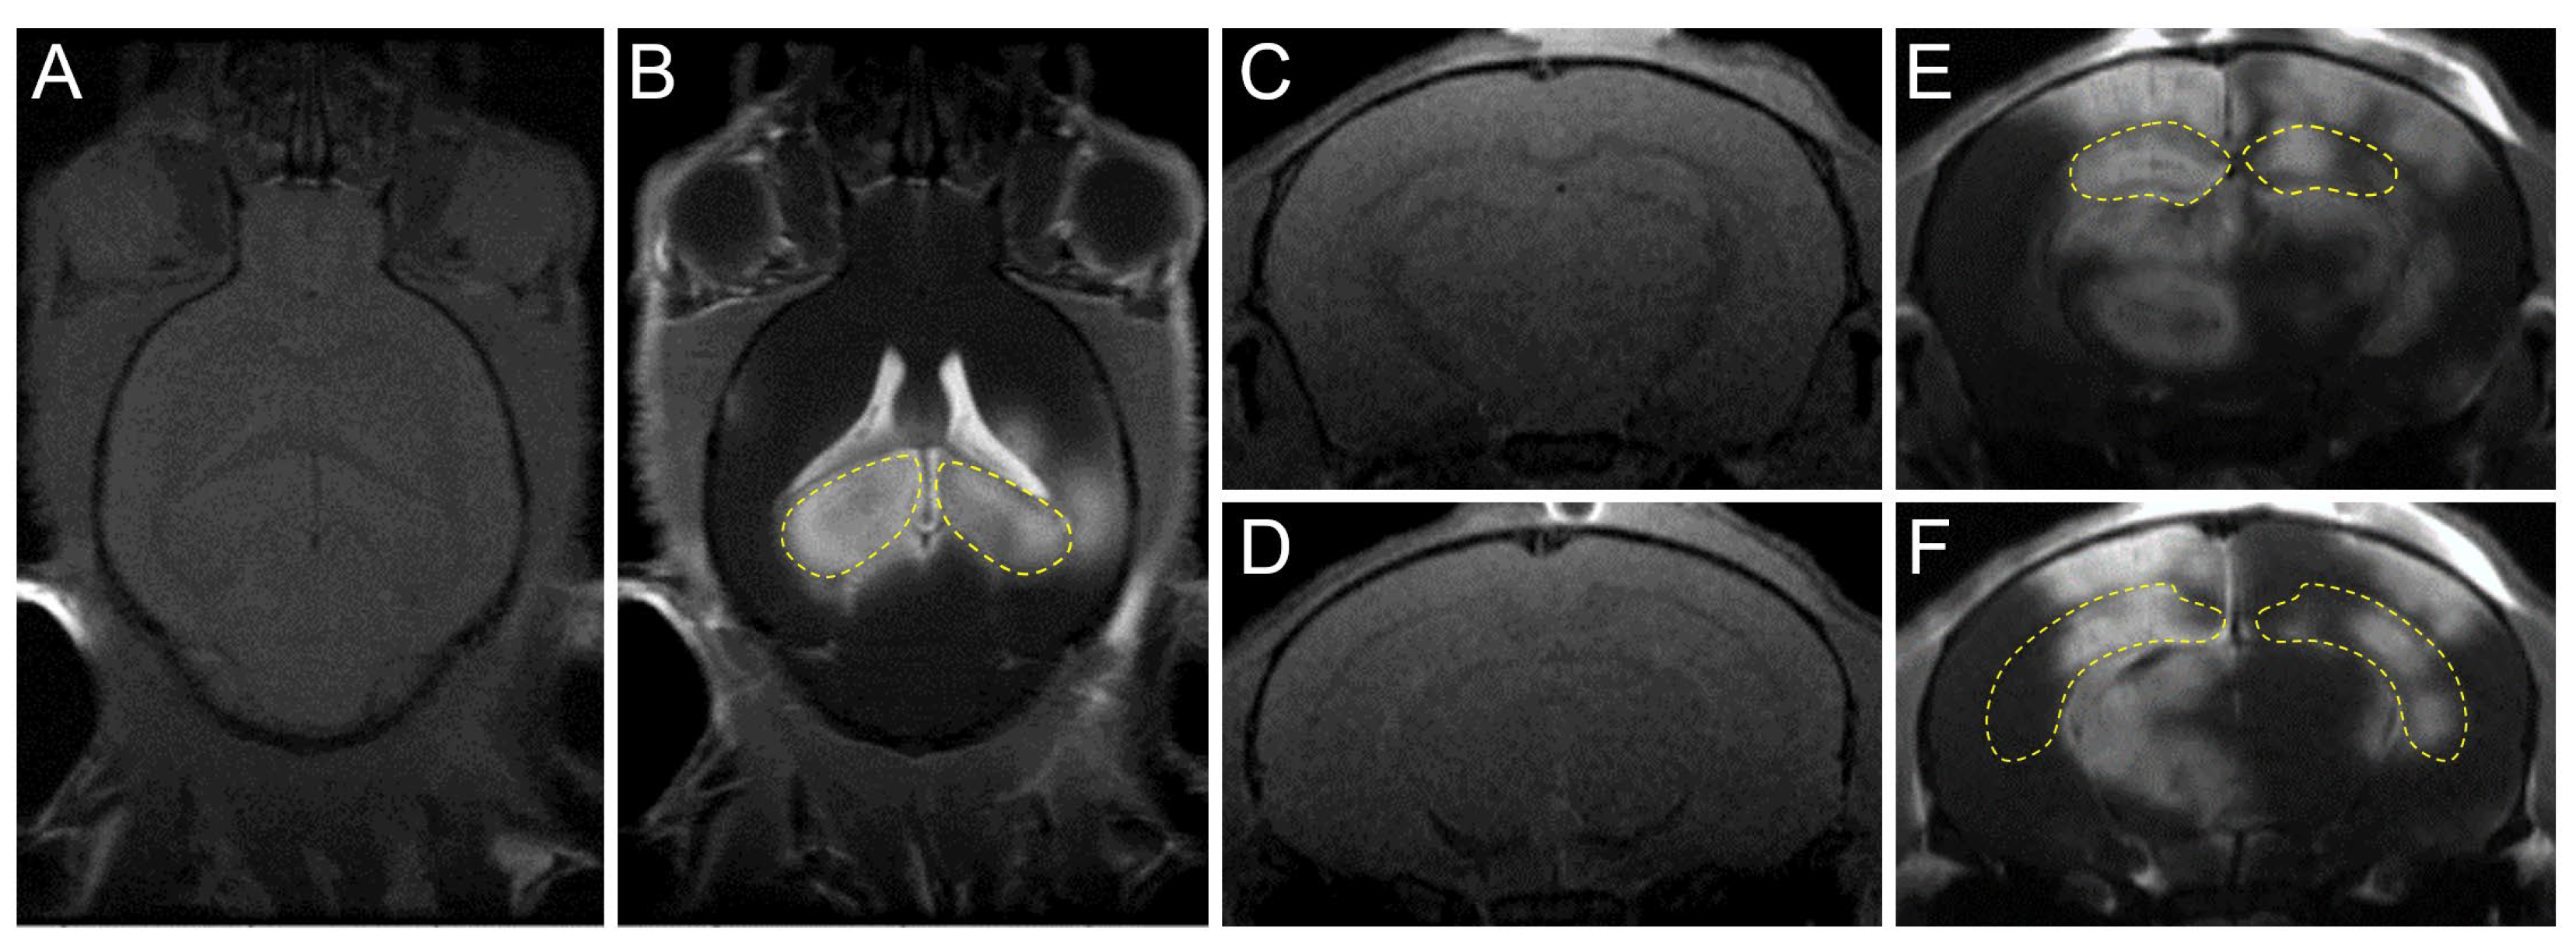

Figure 2.

Confirmation of FUS-induced BBB opening using MRI. The hippocampi (yellow dotted line) of mouse were targeted per sonication. (A,B) Transverse T1-weighted pre-/post-gadolinium MR images were taken to confirm the increased BBB permeability. (C–F) Coronal T1-weighted pre-/post-gadolinium MR images after FUS. (E,F) Coronal T1-weighted post-gadolinium MR images after FUS.